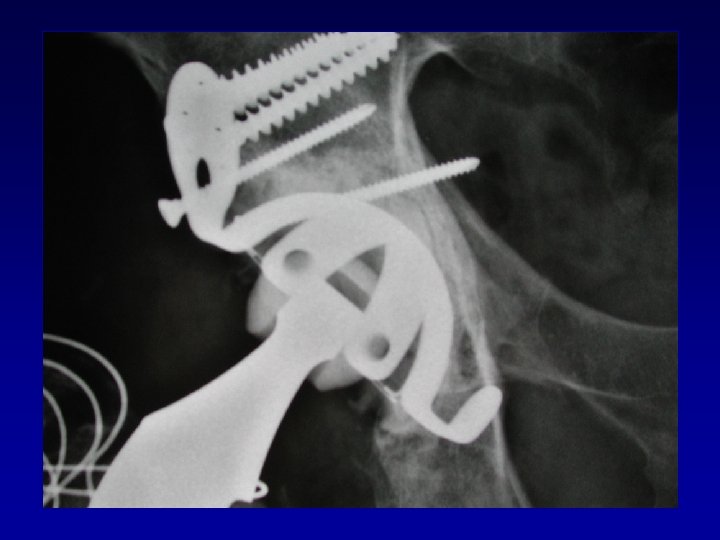

Chirurgie préalable Le matériel en place • Gêne le creusement, la reconstruction Les complications

Chirurgie préalable Le matériel en place • Gêne le creusement, la reconstruction Les complications • Nerveuses : sciatique, crural, fessiers (EMG) • Infectieuses

Arthroplastie totale de hanche sur fracture du cotyle complexe Recentrage, reconstruction, orientation du cotyle

Arthroplastie totale de hanche sur fracture du cotyle complexe Recentrage, reconstruction, orientation du cotyle • • Greffe Ostéosynthèse par plaque MK Surtout si pseudarthrose Réduction de la luxation